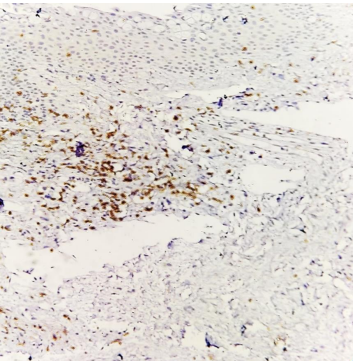

CD3+ cells stained brown (magnification 40X) on immunohistochemistry.